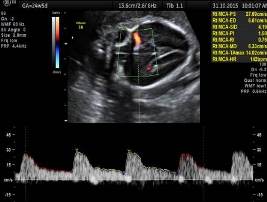

Проанализируйте данные УЗИ и установите диагноз и дальнейшую тактику, надо ли и когда назначить повторное УЗИ для оценки темпов роста?

Допплеровское исследование – нормальный PI в артерии пуповины, средней мозговой артерии, венозном протоке и маточных артериях